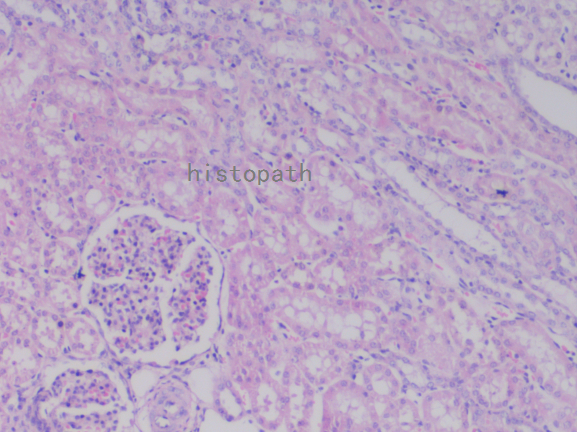

苏木精--伊红染色法(hematoxylin-eosin staining),简称HE染色法,石蜡切片技术里常用的染色法之一。苏木精染液为碱性,主要使细胞核内的染色质与胞质内的核酸着紫蓝色;伊红为酸性染料,主要使细胞质和细胞外基质中的成分着红色。HE染色法使组织学、胚胎学、病理学教学与科研中最基本、使用最广泛的技术方法。

染色结果:

细胞核呈蓝色,细胞质、肌肉、结缔组织、红细胞、嗜曙红颗粒呈不同程度的粉红色。钙盐、软骨基质和各种微生物也可染成蓝色或紫蓝色。核仁呈红色。着色情况不仅与组织或细胞的种类有关,也随其生活周期及病理变化而改变。质量优良的HE染色切片样本,细胞核与细胞质蓝红对比明显,胞核鲜明,核膜及核染色质颗粒均清晰可见。